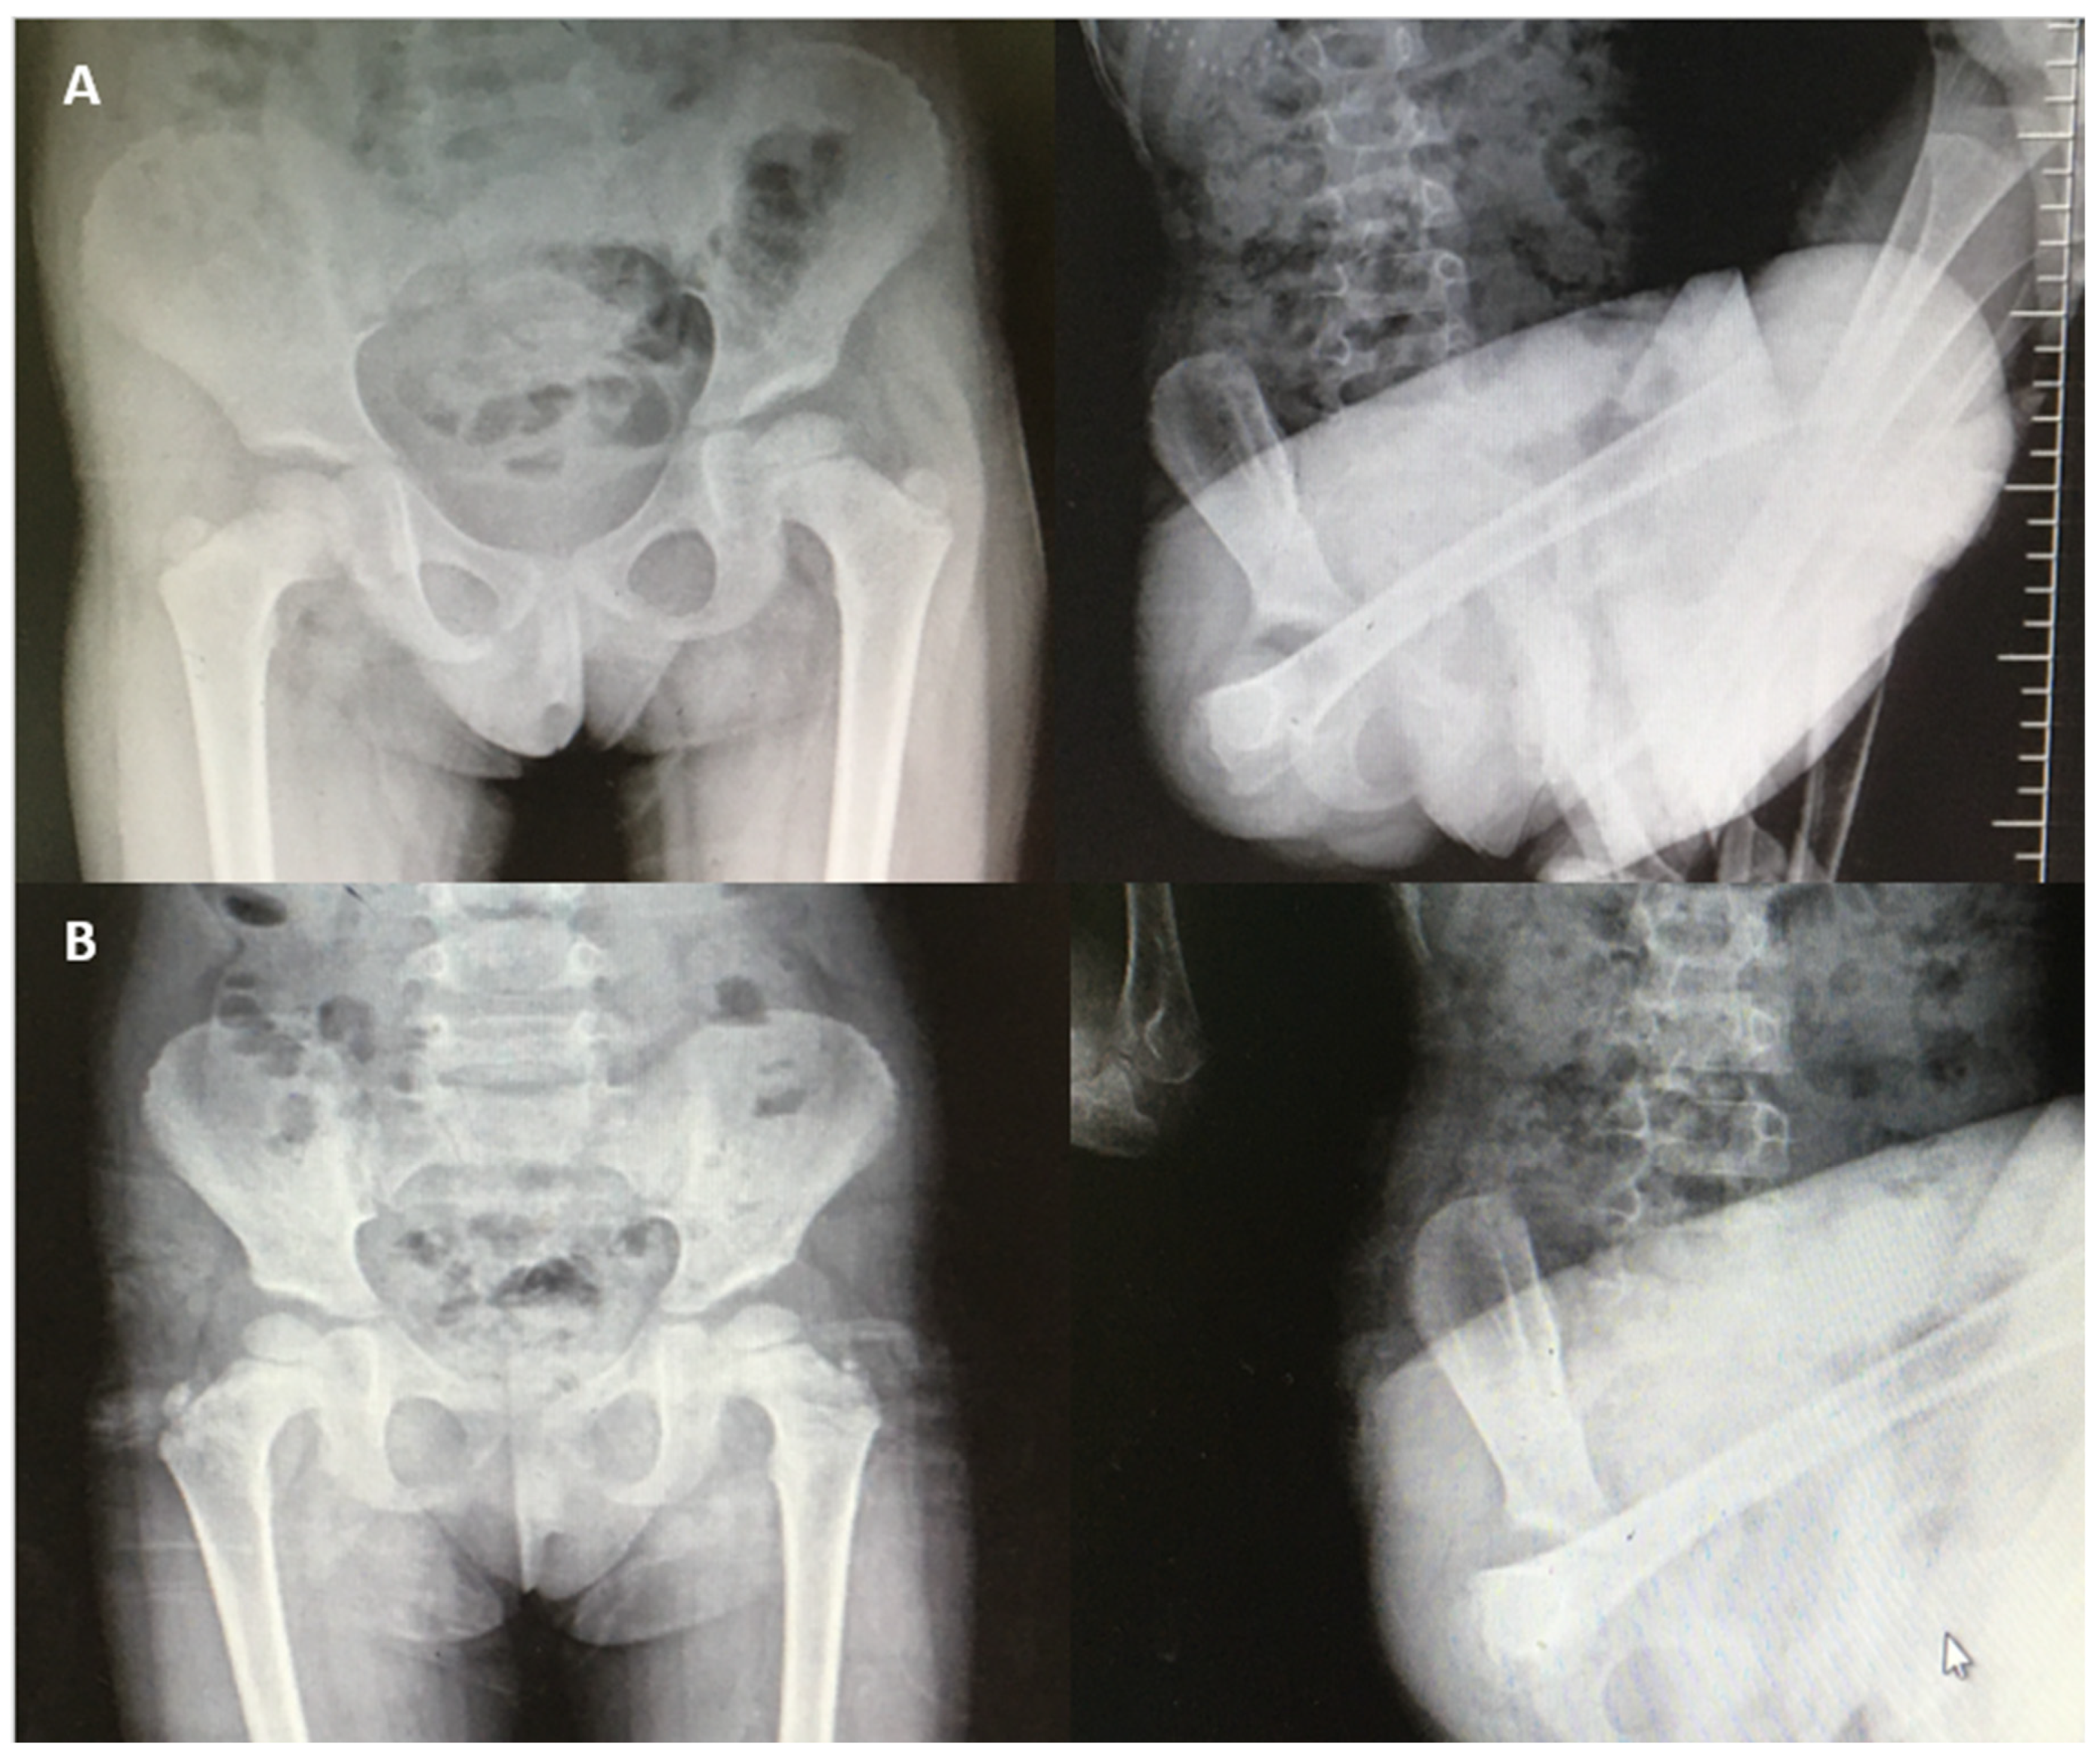

The imaging findings were consistent across the cohort. While computed tomography (CT) scans of the hips in the neutral position showed no structural abnormalities, imaging during dislocation events was not feasible. However, radiographic evaluations confirmed that all dislocations were purely positional, without associated osseous deformities or pathologies. No adverse events or complications were reported during the follow-up period. The conservative management approach demonstrated high efficacy in this cohort, with a favorable long-term prognosis. Figure 1 shows representative radiographs of a patient at the time of dislocation and subsequent reduction in the hip. These findings highlight the importance of considering family dynamics in the treatment plan for voluntary habitual hip dislocations and emphasize the role of multidisciplinary management, including family therapy, in achieving optimal outcomes.

Figure 1. (A) Radiographs showing normal and dislocated hip positions in a 46-month-old female patient. (B) Radiographs showing normal and dislocated hip positions in a 54-month-old female patient.